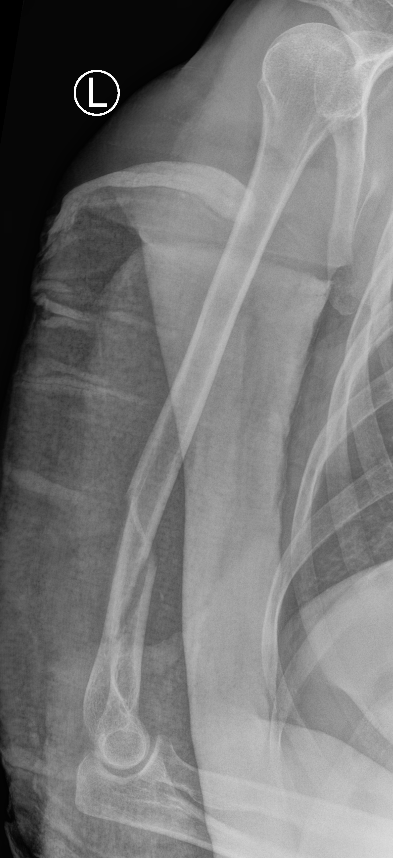

Union of a midshaft humerus fracture treated nonoperatively

Union of distal humerus fracture treated nonoperatively